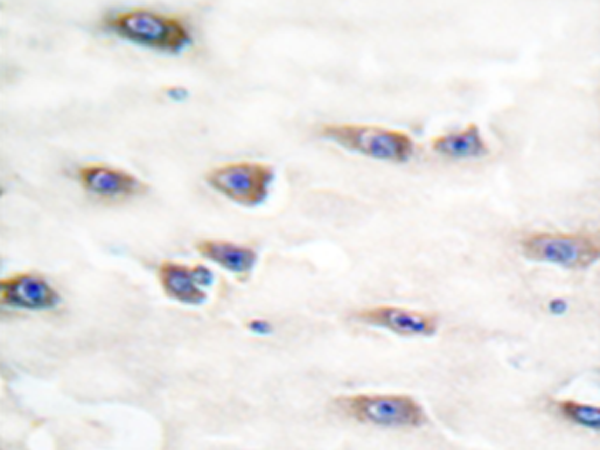

This gene encodes a member of the neurotrophic tyrosine kinase receptor (NTKR) family. This kinase is a membrane-bound receptor that, upon neurotrophin binding, phosphorylates itself and members of the MAPK pathway. The presence of this kinase leads to cell differentiation and may play a role in specifying sensory neuron subtypes. Mutations in this gene have been associated with congenital insensitivity to pain, anhidrosis, self-mutilating behavior, mental retardation and cancer. |

IHC |

IHC positive control: |

Human brain tissue |

IHC Recommend dilution: |

50-100 |